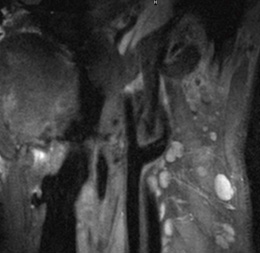

図2に,頸動脈血管壁病変(プラーク)へのMSDE法の臨床応用例を示す。図2 aは,DIR(従来)法によるT1強調BBIで,データ収集には2Dのturbo spin echo法を用いている(2D-DIR-TSE)。図2 bは,MSDE法によるT1強調BBIで,データ収集には3D turbo field echo法を用いている(3D-MSDE-TFE)。両手法ともに同様のコントラストを呈しており,血液抑制効果も良好である。また,矢印(↑)に示すように,両手法ともプラークを高信号として描出している。ただし,2D-DIR-TSEの撮像時間が17s/imageであるのに対して,3D-MSDE-TFEの撮像時間は9s/imageとなり,2倍の撮像時間短縮効果が得られている。図3は,頸動脈の血管走行に沿った撮像断面での2D-MSDE-TSE画像である。撮像面内に血管を含んでいる場合でも,血液は全撮像範囲において抑制されている。

図3 in plane BBI画像

頸動脈の血管走行に沿った撮像断面での2D-MSDE-TSE画像。撮像面内に血管を含んでいる場合でも,血液は全撮像範囲において抑制されている。

(画像ご提供:東北大学様)